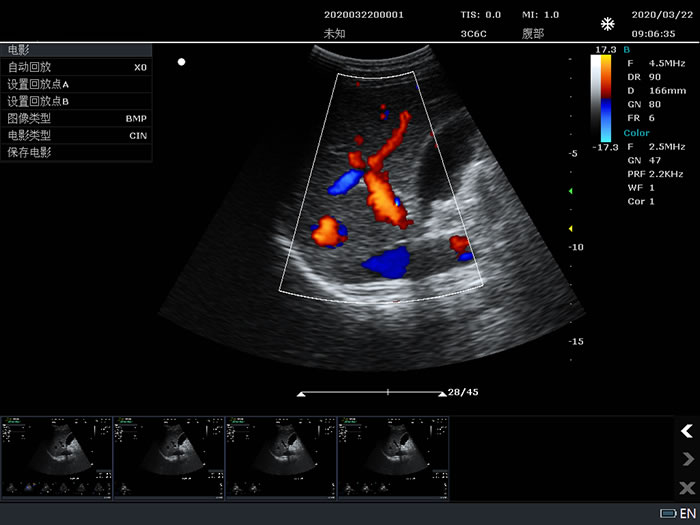

3C6C: 3.5MHz/R60/128,Convex array probe

Color Flow Mapping (Color)

Power Doppler Imaging (PDI)

3C6C: 3.5MHz/R60/128,Convex array probe

B-mode: Fundamental and Tissue harmonic imaging

Color Flow Mapping (Color)

B/BC Dual Real-Time

Power Doppler Imaging (PDI)